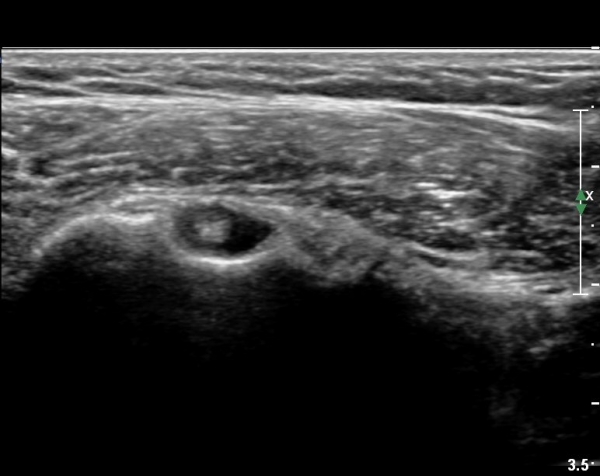

ŽÃËÀÚ¸¦ Á¶±Ý ¾Æ·¡·Î À̵¿ÇÏ¿© À̵ιڱٰÇÀÇ È¾´Ü¸é°Ë»ç¿¡¼­ ÀÌµÎ¹Ú±Ù°Ç ÁÖÀ§ ¼ö¾×Àú·ù°¡ °üÂûµÈ´Ù(»çÁø 3, 4).

À̴ Ȱ¾×¸·¿°Áõ ¼Ò°ßÀ¸·Î Ãæµ¹ÁõÈıº ¶Ç´Â ȸÀü±Ù°³ ÆÄ¿­ ½Ã ÈçÈ÷ °üÂûµÇ´Â

¼Ò°ßÀÌ´Ù.